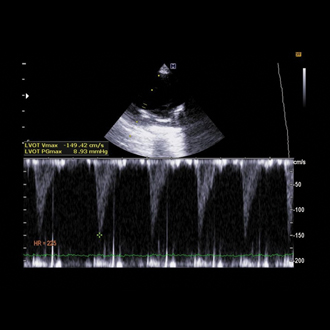

PDA 심장 혈관기형 수술

선천적으로 남아있는 혈관(동맥관) 때문에 심장에 과부하가 생기는 경우, 문제 혈관을 안전하게 교정하는 수술입니다.

빠른 진단과 적절한 수술 시기가 예후에 중요합니다.